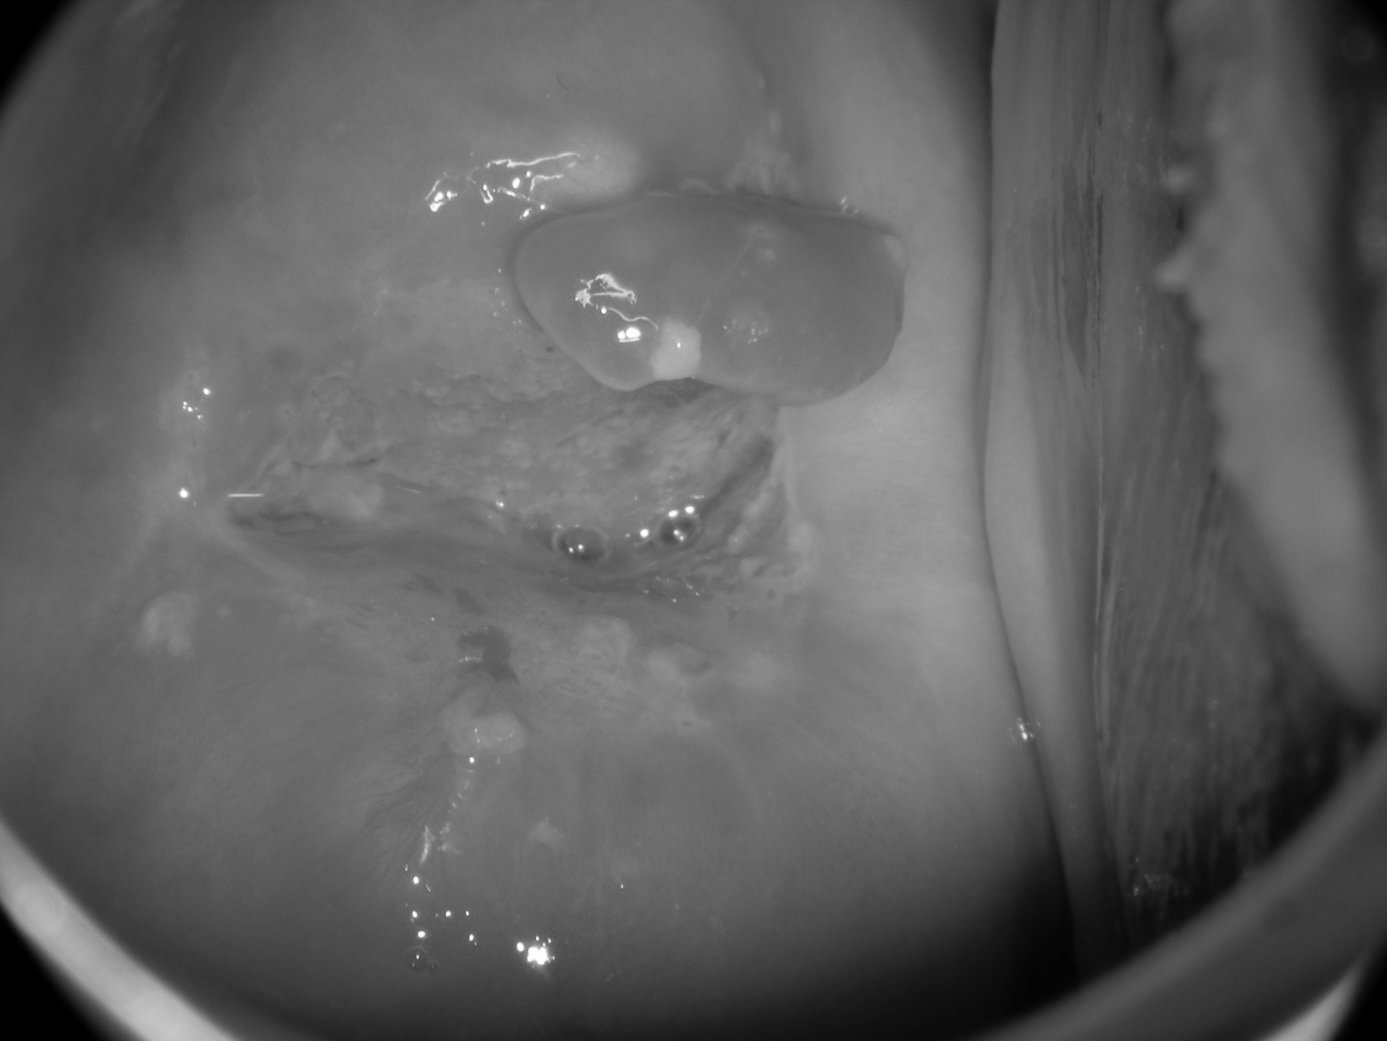

5 . 2  -  Polypes

Il s’agit d’une tumeur muqueuse plus ou moins volumineuse pouvant se manifester par des saignements au contact ou une sur-infection (figure 18.11).

Figure 18.11 Polype muqueux implanté sur la lèvre antérieure du col

Figure 18.11 Polype muqueux implanté sur la lèvre antérieure du col.

Selon la taille et la situation de la base d’implantation, le traitement peut se faire par simple bistournage (exérèse par plusieurs tours de spire) ou au bistouri sous analgésie.

Chez la femme ménopausée, ils imposent une vérification de la cavité utérine, en échographie (en particulier hystérosonographie) ou en hystéroscopie, à la recherche d’autres polypes.